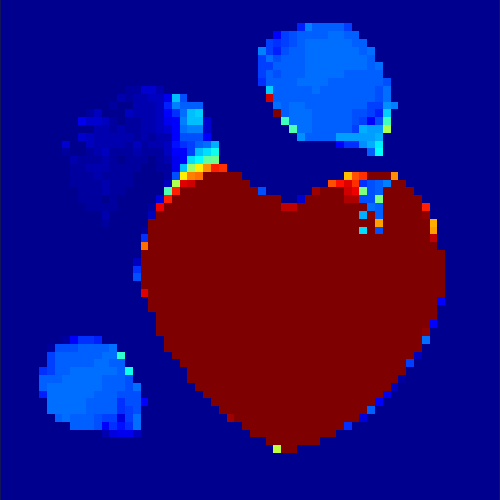

The first data set consists of a heart-shaped region and three circles on a static background (see figure 1 (a)). The two smaller circles are assumed to belong to

the same tissue type and therefore to the same subregion, which causes a total of four subregions, including the background. To simulate a more realistic application of dynamic SPECT

imaging, we used a synthesized representation of a rat liver as a second data set (see figure 1 (b)). The temporal concentration curves used to simulate the data sets

are shown in figure 2. As before, the total number of subregions was chosen to be equal to four in order to provide a both simple and realistic shape model.

In a first test, every image sequence was reconstructed out of the exact given sinograms. Additionally we tested noise corrupted data by first scaling the sinogram by a parameter , corrupting them with Poisson noise via the MATLAB imaging toolbox command imnoise and finally rescaling the image to the original range (see figure 4). The average count number per time step (i.e. the average of the discrete -norm of the data at each time step) is approximately in case of the heart-shaped data set and ca. in case of the rat liver simulation. The results at a certain number of time steps can be seen in figure 6 and 7. For comparison, we additionally performed a reconstruction with a simple alternating EM method, keeping the assumption that the tracer can be modelled as a sum of indicator functions and subconcentration curves, but neglecting any regularization terms. In all tests, the outer iteration number was set to 1000 with 10000 inner iterations per subproblem, to obtain a result within a reasonable time period. As stopping criterion, we chose the primal dual residual (cp. [12]) for the inner and the maximum over the Frobenius norms of and for the outer iterations. The results are displayed in 6 and 7 respectively.

As one can see in both figures, the reconstruction method applied to each data set performs very well, especially in contrast to the simple alternating EM method. This clearly shows the benefits of the proposed regularization methods. In case of noise-free given data, the shape of every object, where especially the heart is of higher interest, is clearly defined. As expected, we often observe errors in the edges of each region and where two regions are directly connected (the heart and the upper left circle). This causes the algorithm to incorrectly assign these pixels to another region. Furthermore, the reconstruction difficulties increase with an increase in noise. Some more pixels are assigned to the wrong region, which leads to a small hole-like structure within the heart region and causes a slight blurring effect. In the second data set the method clearly outperforms several other approaches by providing very clearly defined regions and even reconstructing fine structures of the phantom. However, as mentioned before, a clear reconstruction of the rat liver required highly optimized parameter sets, which makes the whole problem quite susceptible to parameter changes.